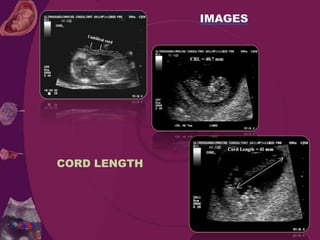

Cord begins to form at 5 weeks of gestation it becomes longer until

28 weeks of pregnancy until it reaches average length of 22 to 24

inches (55 -60 cm.).

Normal cord length is 50-60 cm.

CORD LENGTH